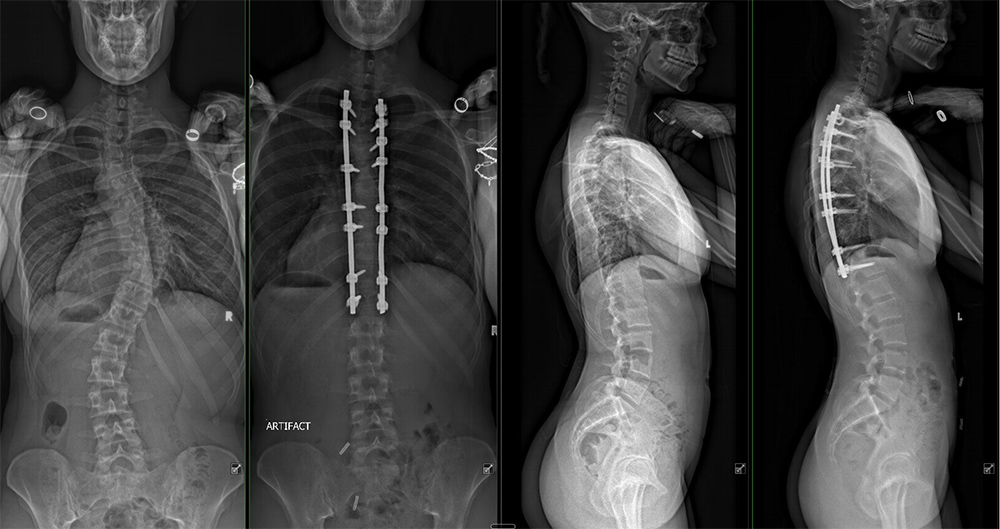

Milan Brahney's X-rays before and after surgery.

“When Milan came to us, she had three curves in her back, the largest of which was severe, at 53 degrees,” Skaggs said. “Left untreated, it would continue to get one degree worse every year for the rest of her life—eventually leaving her with a huge bump on her back, unable to take a full breath and in a lot of pain.”

When the day finally came for Skaggs to correct Brahney’s scoliosis, he made a single incision—just over ten inches long—down the midline of her back. Through this approach, he placed titanium screws roughly a quarter-inch wide and 1.5 inches long into the vertebrae.

“These are titanium screws, and they must be placed with millimeter precision,” said Skaggs. “It’s a fine art. You want a surgeon who has done it thousands of times and knows how to get it right.”

Skaggs and his assistant then gradually and safely straightened Brahney’s spine, and the team secured it with cobalt-chrome rods contoured to match the spine’s natural shape.

The surgery was a success, and eventually, Brahney’s vertebrae will fuse together, supported by the screws and rods.

“They immediately did an X-ray of my back lying down,” she said. “I was really out of it, but I remember looking at it and thinking, ‘Oh my gosh, that’s my spine. It’s straight!’”